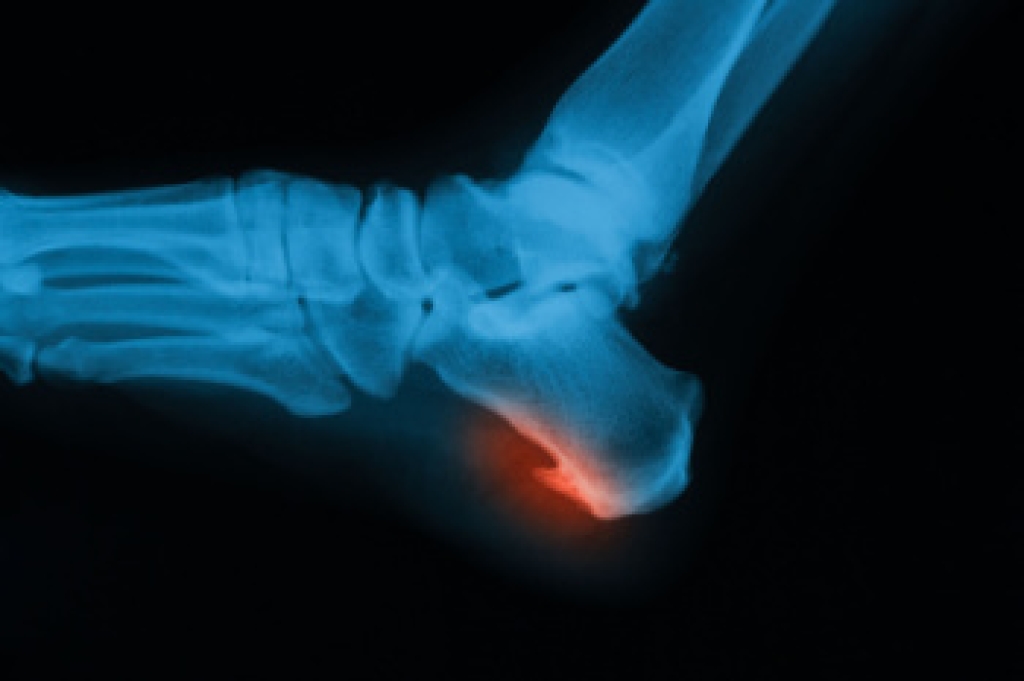

The feet contain 26 bones each, creating numerous joints and surfaces where bone spurs may develop from repeated stress, inflammation, or injury. These bony growths, known as osteophytes, often form when the body responds to pressure or friction. If conservative care does not ease symptoms, a podiatrist may suggest surgery to remove the bone spur or address any tight tissues that may be contributing to discomfort. Resection surgery trims away the excess bone, and the type depends on the location. A dorsal spur excision is on the top of the foot, an inferior heel spur resection is under the heel, and a posterior heel spur removal is at the back of the heel. If soft tissue is involved, plantar fascia release or partial Achilles tendon release may be employed. In cases of severe joint damage, joint fusion can stabilize the area while joint replacement can restore movement. If you are experiencing this type of foot pain, it is suggested that you schedule an appointment with a podiatrist for an exam and appropriate treatment options.